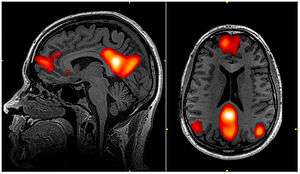

Dynamic functional connectivity (DFC) refers to the observed phenomenon that functional connectivity changes over a short time. Dynamic functional connectivity is a recent expansion on traditional functional connectivity analysis which typically assumes that functional networks are static in time. DFC is related to a variety of different neurological disorders, and has been suggested to be a more accurate representation of functional brain networks. The primary tool for analyzing DFC is fMRI, but DFC has also been observed with several other mediums. DFC is a recent development within the field of functional neuroimaging whose discovery was motivated by the observation of temporal variability in the rising field of steady state connectivity research

Functional connectivity refers to the functionally integrated relationship between spatially separated brain regions. Unlike structural connectivity which looks for physical connections in the brain, functional connectivity is related to similar patterns of activation in different brain regions regardless of the apparent physical connectedness of the regions.[1] This type of connectivity was discovered in the mid-1990s and has been seen primarily using fMRI and Positron emission tomography.[2] Functional connectivity is usually measured during resting state fMRI and is typically analyzed in terms of correlation, coherence, and spatial grouping based on temporal similarities.[3] These methods have been used to show that functional connectivity is related to behavior in a variety of different tasks, and that it has a neural basis. These methods assume the functional connections in the brain remain constant in a short time over a task or period of data collection.

Because DFC is such a new field, much of the research related to it is conducted to validate the relevance of these dynamic changes rather than explore their implications; however, many critical findings have been made that help the scientific community better understand the brain. Analysis of dynamic functional connectivity has shown that far from being completely static, the functional networks of the brain fluctuate on the scale of seconds to minutes. These changes are generally seen as movements from one short term state to another, rather than continuous shifts.[3] Many studies have shown reproducible patterns of network activity that move throughout the brain. These patterns have been seen in both animals and humans, and are present at only certain points during a scanner session.[7] In addition to showing transient brain states, DFC analysis has shown a distinct hierarchical organization of the networks of the brain. Connectivity between bilaterally symmetric regions is the most stable form of connectivity in the brain, followed by other regions with direct anatomical connections. Steady state functional connectivity networks exist and have physiological relevance, but have less temporal stability than the anatomical networks. Finally, some functional networks are fleeting enough to only be seen with DFC analysis. These networks also possess physiological relevance but are much less temporally stable than the other networks in the brain.[8]